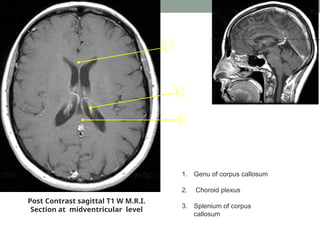

Post Contrast sagittal T1 W M.R.I.

Section at midventricular level

1. Genu of corpus callosum

2. Choroid plexus

3. Splenium of corpus

callosum